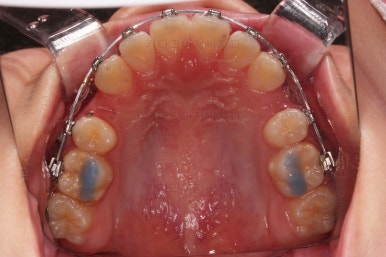

초진 시, 입 안의 모습입니다.

치아가 많이 삐뚤어요.

공간이 부족해서 앞니가 앞으로 많이 뻐드러졌고, 삐뚤한 양상 때문에 덧니가 되었네요.

어금니 맞물림도 좋지 못한 앵글씨 2급 부정교합 상태였어요.

이번 환자분이 선택하신 장치는 엠파워 메탈이라고 하는 자가결찰 메탈장치에요.

자가(스스로) 결찰(철사를 잡아주는 캡이 달려있는) 메탈(금속성분의) 장치라는 뜻인데요.

메탈이라고 옛날 장치가 아니라 자가결찰인지 아닌지가 훨신 중요하답니다.

부산덧니교정 치료방법은 발치교저이며 윗니를 훨씬 많이 당겨줘야하기 때문에 미느스크류를 보조적으로 사용했어요.

장치 부착 직후의 모습인데요.